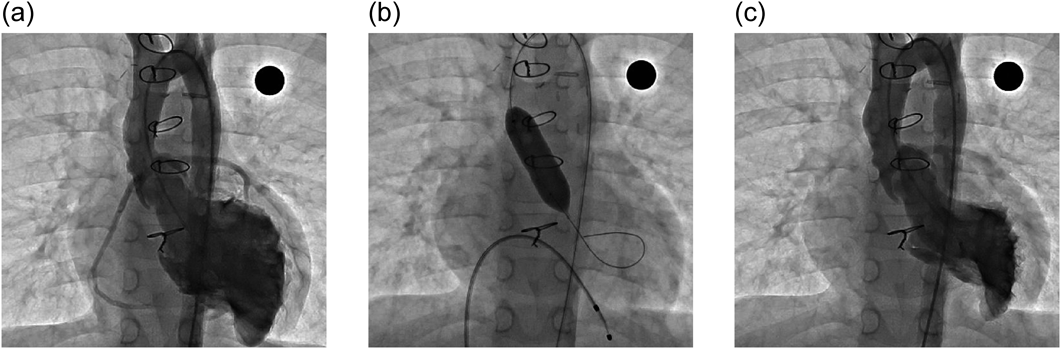

Fig. 2にファロー四徴症術後に左肺動脈狭窄をきたした1歳女児例を示す.最狭窄部径3.5 mm,参照血管径6.1 mmの左肺動脈狭窄に対し,径9 mmの超高耐圧バルーンによるバルーン肺動脈形成術を行った.バルーン肺動脈形成術後の造影では,左肺動脈狭窄の解除が確認された.

Fig. 2 A 1-year-old female infant with left pulmonary artery stenosis following repair of Tetralogy of Fallot

(a) Severe stenosis is observed in the proximal portion of the left pulmonary artery. The diameter of the stenotic site was 3.5 mm, and the diameter of the distal left pulmonary artery was 6.1 mm. (b) Pulmonary artery angioplasty using an ultra-high-pressure balloon (9 mm). The disappearance of the waist was observed. (c) Pulmonary artery angiography after pulmonary artery angioplasty. The stenosis in the proximal portion of the left pulmonary artery has improved.